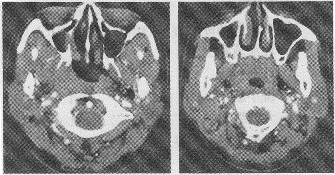

男,51歲,發現鼻塞、耳鳴、聽力減退及右側頸部包塊一個月余。查體示右頸部多發質硬包塊。

2.患者已行頸部CT掃描,主要圖像如下,結合CT表現,最可能的診斷為

正確答案:1.C;2.C;3.ABCDE;4.ABCE;5.C 解題思路:鼻咽癌好發于40~60歲者,男性多于女性,已知的發病因素有種族、家族因素,EB病毒感染及環境致癌因素。本病特點是早期癥狀隱蔽,常因廣泛浸潤周圍組織及發生淋巴結轉移后才發現,主要癥狀有鼻阻塞、鼻衄、耳鳴、耳悶塞及聽力減退,鼻咽及其鄰近結構如鼻及鼻竇腫瘤均可有以上癥狀,CT表現有鼻咽變形、不對稱、咽隱窩消失,鼻咽側壁軟組織腫塊,淋巴結轉移多見于頸深淋巴結、咽后外側淋巴結。MRI對鑒別腫瘤復發有重要價值,正確率可達80%以上。